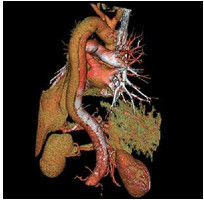

主動脈夾層此外,Daily和Miller又將主動脈夾層分為兩型:凡升主動脈受累者為A型(包括DeBakeyⅠ型和Ⅱ型),病變在左鎖骨下動脈遠端開口為B型(即DeBakeyⅢ型),A型約占全部病例的2/3,B型約占1/3。

主動脈夾層動脈瘤(二)X線 胸部平片見上縱隔或主動脈弓影增大,主動脈外形不規則,有局部隆起。如見主動脈內膜鈣化影,可準確測量主動脈壁的厚度。正常在2~3mm,增到10mm時則提示夾層分離可能性,若超過10mm則可肯定為本病。主動脈造影可以顯示裂口的部位,明確分支和主動脈瓣受累情況,估測主動脈瓣關閉不全的嚴重程度。缺點是它屬於有創性檢查,術中有一定危險性。CT可顯示病變的主動脈擴張。發現主動脈內膜鈣化優於X線平片,如果鈣化內膜向中央移位則提示主動脈夾層,如向外圍移位提示單純主動脈瘤。此外CT還可顯示由於主動脈內膜撕裂所致內膜瓣,此瓣將主動脈夾層分為真腔和假腔。CT對降主動脈夾層分離準確性高,主動脈升、弓段由於動脈扭曲,可產生假陽性或假陰性。但CT對確定裂口部位及主動脈分支血管的情況有困難,且不能估測主動脈瓣關閉不全的存在。

(四)磁共振成像(MRI) MRI能直接顯示主動脈夾層的真假腔,清楚顯示內膜撕裂的位置和剝離的內膜片或血栓。能確定夾層的範圍和分型,以及與主動脈分支的關係。但其不足是費用高,不能直接檢測主動脈瓣關閉不全,不能用於裝有起搏器和帶有人工關節、鋼針等金屬物的病人。

StanfordA型(相當於DebakeyI型和II型)需要外科手術治療。DebakeyI型手術方式為升主動脈+主動脈弓人工血管置換術+改良支架象鼻手術。DebakeyII型手術方式為升主動脈人工血管置換術。